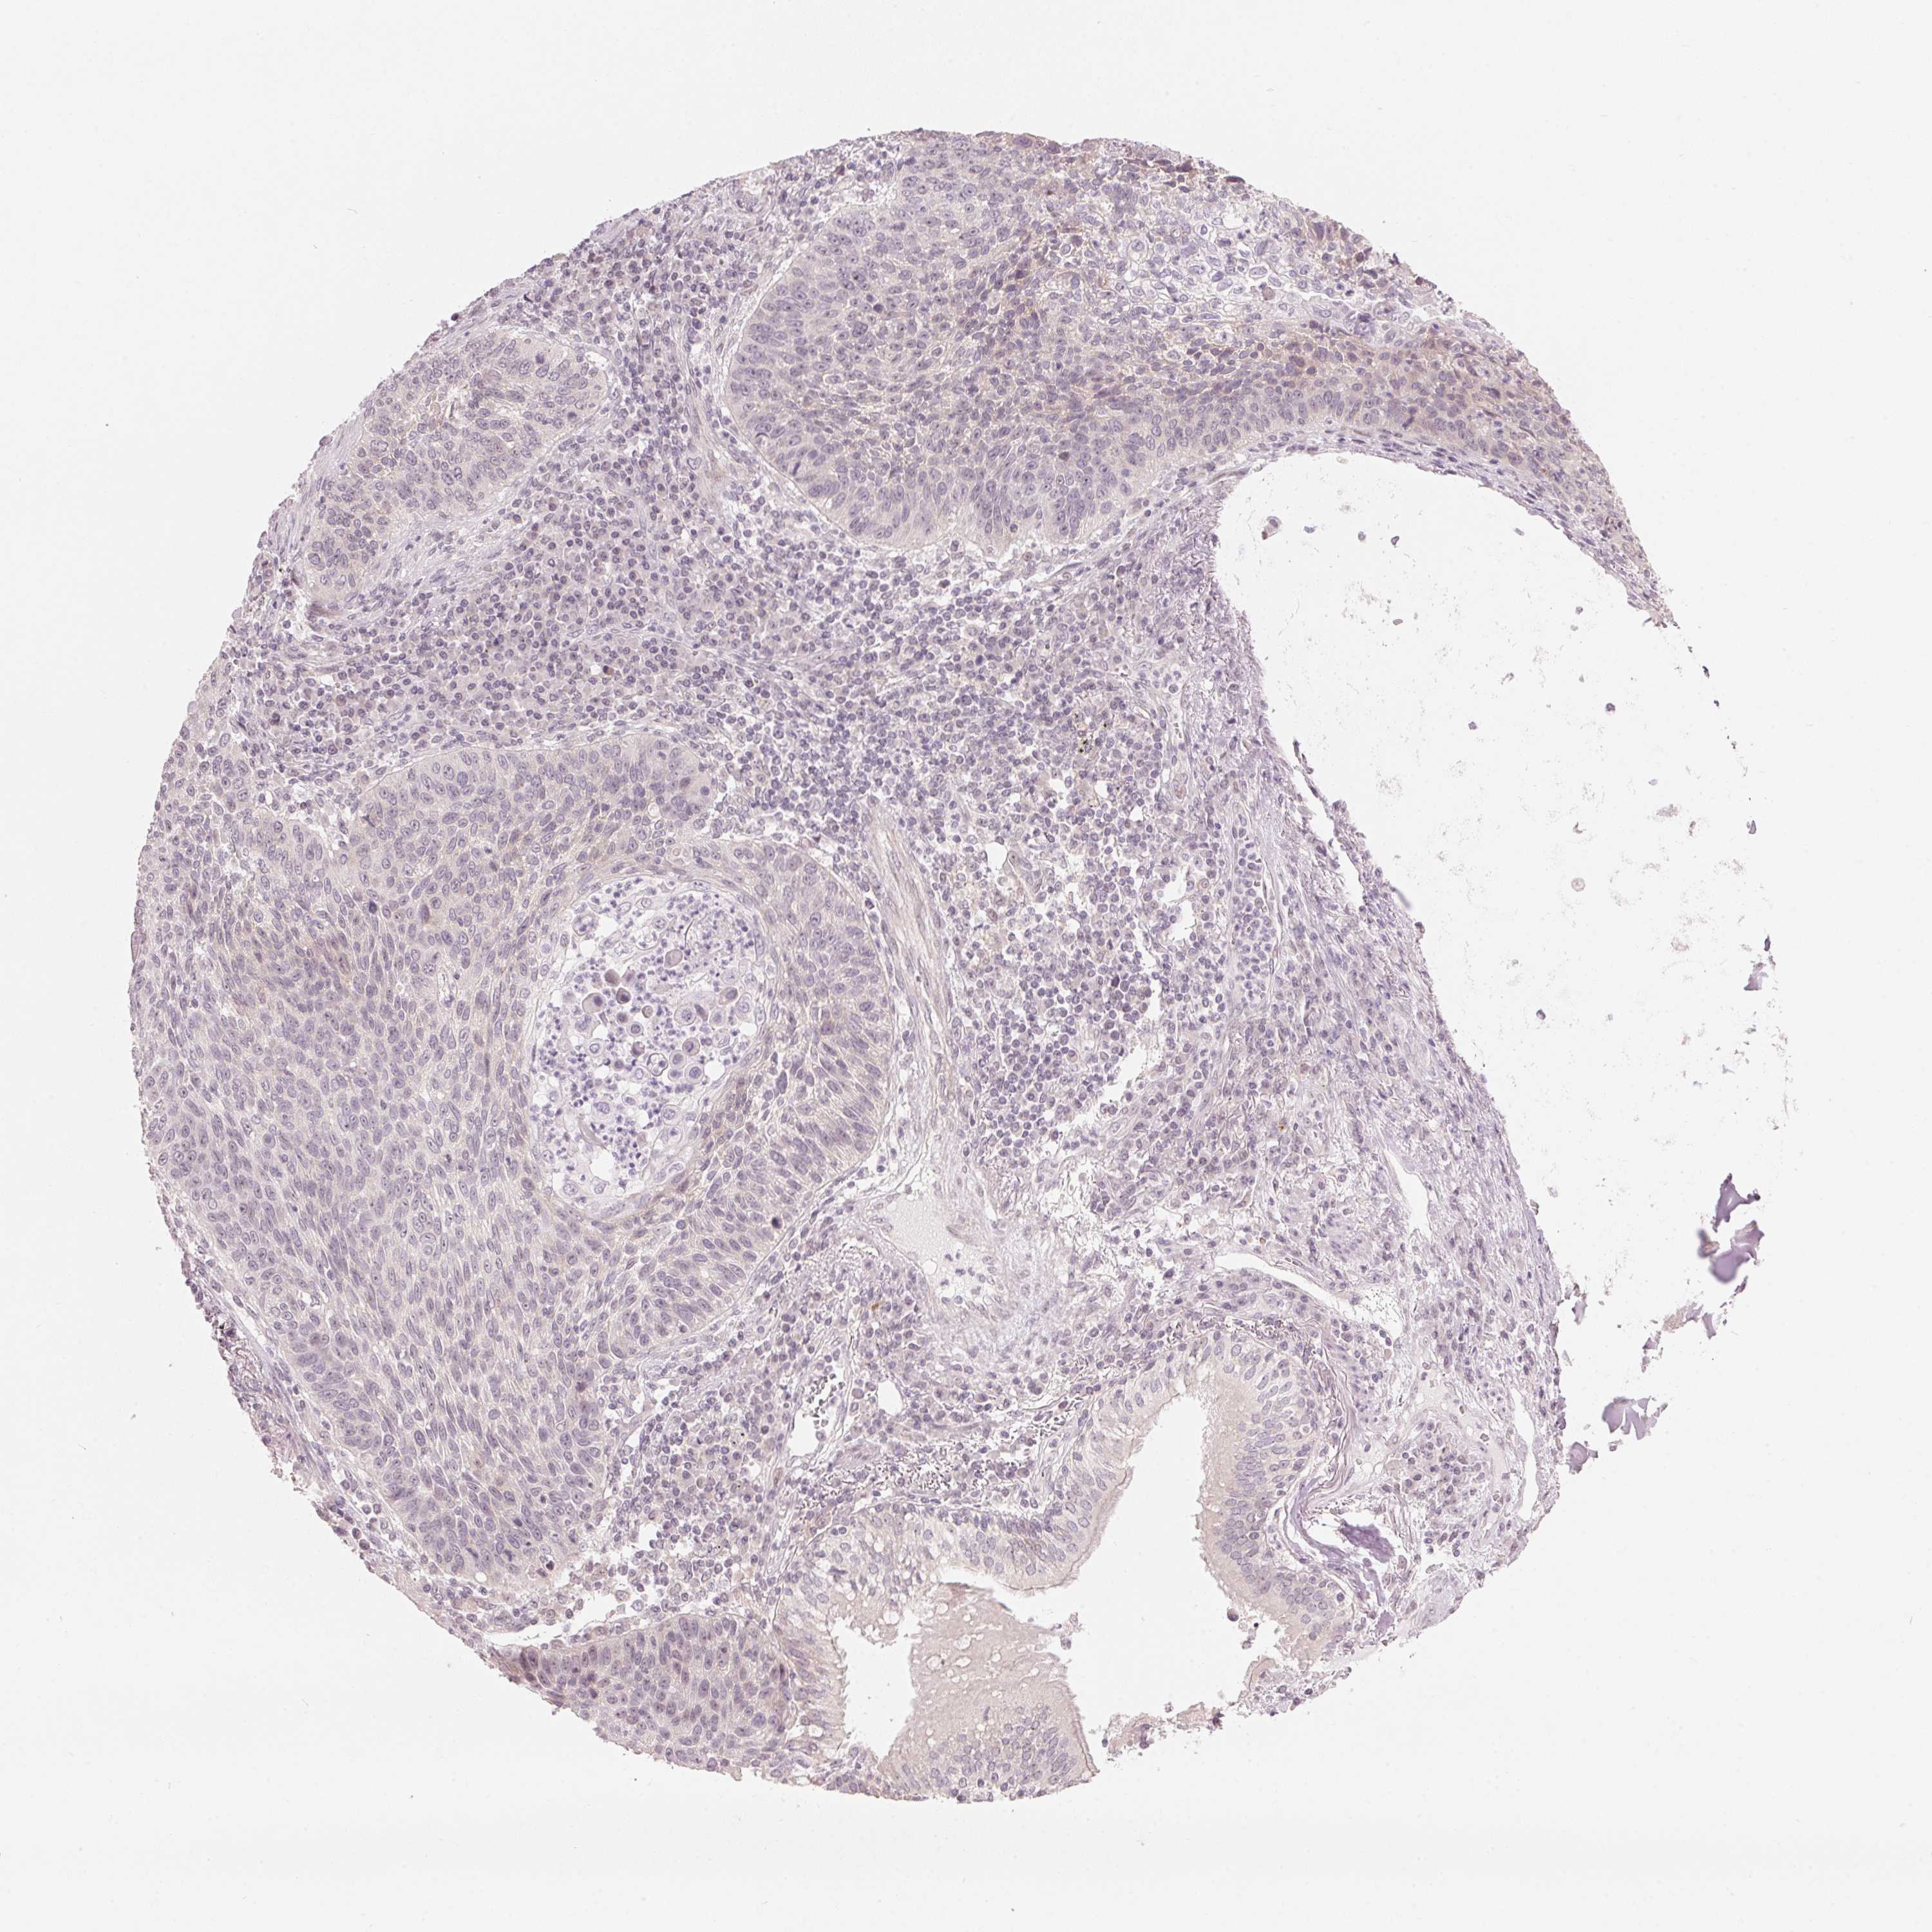

CANCER LUNG CANCER Show tissue menu

Lung cancer

Human cancer

Lung adenocarcinoma

Lung squamous cell carcinoma